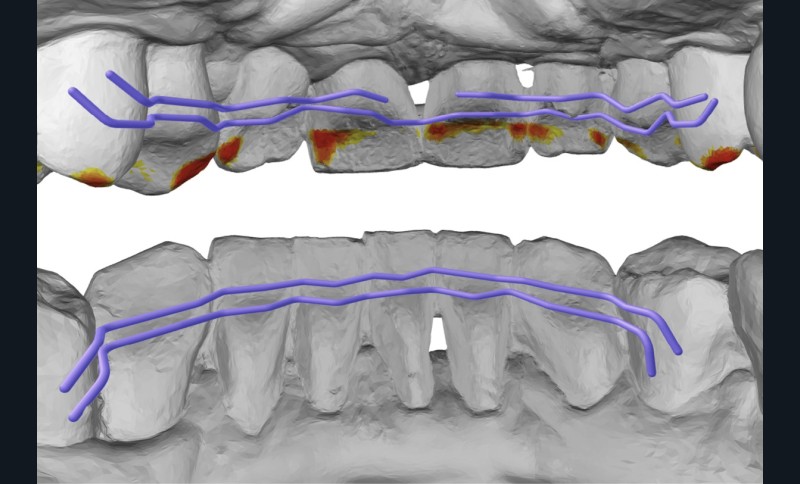

La contention collée de fin de traitement a consisté en plusieurs fils TMA .016 étendus jusqu’aux premières prémolaires, afin de limiter la mobilité des dents antérieures et empêcher la réouverture des diastèmes. Ces fils ont été modélisés numériquement et pliés par robot (société Winnove Medical, Rennes, France), permettant de s’assurer de l’absence de visibilité des fils dans les espaces inter-dentaires et limiter les prématurités occlusales (fig. 14). Des gouttières de contention thermoformées sont réalisées en cas de casse ou décollement des fils, afin de prévenir une éventuelle réouverture des diastèmes.